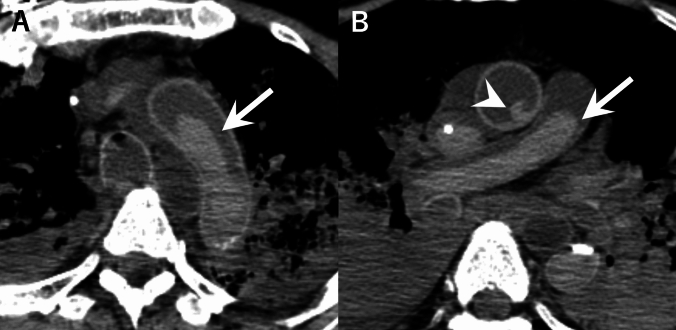

目的:尸体计算机断层扫描(PMCT)通常显示心脏和血管结构中的血凝块和沉淀。我们检查了这些死后发现与院内死亡的死前临床和实验室参数之间的关系。材料和方法:这项前瞻性研究包括114例死后24小时内进行PMCT的非创伤性院内死亡。两名放射科医生评估了左右心房、肺动脉和胸主动脉的高密度区域,并将其分类为血凝块或重力沉降。采用单因素和多因素logistic回归分析死亡前一周的临床和实验室数据。结果:所有解剖部位的观察者间一致性极好(κ = 0.87-0.91)。34-53%的病例在不同部位观察到血凝块或血液沉淀。根据单因素分析,非肺炎感染、阳性血培养和升高的凝血参数(凝血酶原时间-国际标准化比率、活化的部分凝血活酶时间)与重力沉降有关。相反,实体恶性肿瘤和较高的血液学参数(血小板计数、红细胞、血红蛋白、中性粒细胞百分比)与血块形成相关(均p)。结论:死后重力沉降与非肺炎感染有关,而血块形成与较高的血小板计数有关。这些发现为解释PMCT的发现提供了客观标准,并可能有助于评估患者生前的临床状态,特别是在临床信息有限的情况下。

Material and methods: This prospective study included 114 non-traumatic in-hospital deaths where PMCT was performed within 24 h postmortem. Two radiologists evaluated high-density areas in the right and left atria, pulmonary artery, and thoracic aorta, and classified them as blood clots or gravitational sedimentation. The clinical and laboratory data from the week before death were analyzed using univariate and multivariate logistic regression.

Results: Interobserver agreement was excellent for all anatomical sites (κ = 0.87-0.91). Blood clot or blood sedimentation were observed in 34-53% of cases across different locations. Per univariate analysis, non-pneumonic infections, positive blood cultures, and elevated coagulation parameters (prothrombin time-international normalized ratio, activated partial thromboplastin time) were associated with gravitational sedimentation. In contrast, solid malignancies and higher values of hematologic parameters (platelet count, red blood cells, hemoglobin, neutrophil percentage) were associated with blood clot formation (all p < .05). Per multivariate analysis, non-pneumonic infections maintained strong associations with gravitational sedimentation across all sites (p < .05), while higher platelet counts independently predicted blood clot formation in the right atrium, left atrium, and thoracic aorta (p < .05).

Conclusion: Postmortem gravitational sedimentation was associated with non-pneumonic infections, whereas clot formation correlated with higher platelet counts. These findings provide objective criteria for interpreting PMCT findings and may aid in evaluating patients' antemortem clinical status, particularly when clinical information is limited.